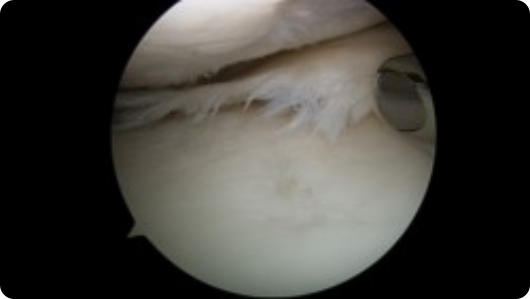

Arthroscopic image of a shoulder dislocation Arthroscopic image of a repaired shoulder dislocation

Shoulder Dislocation